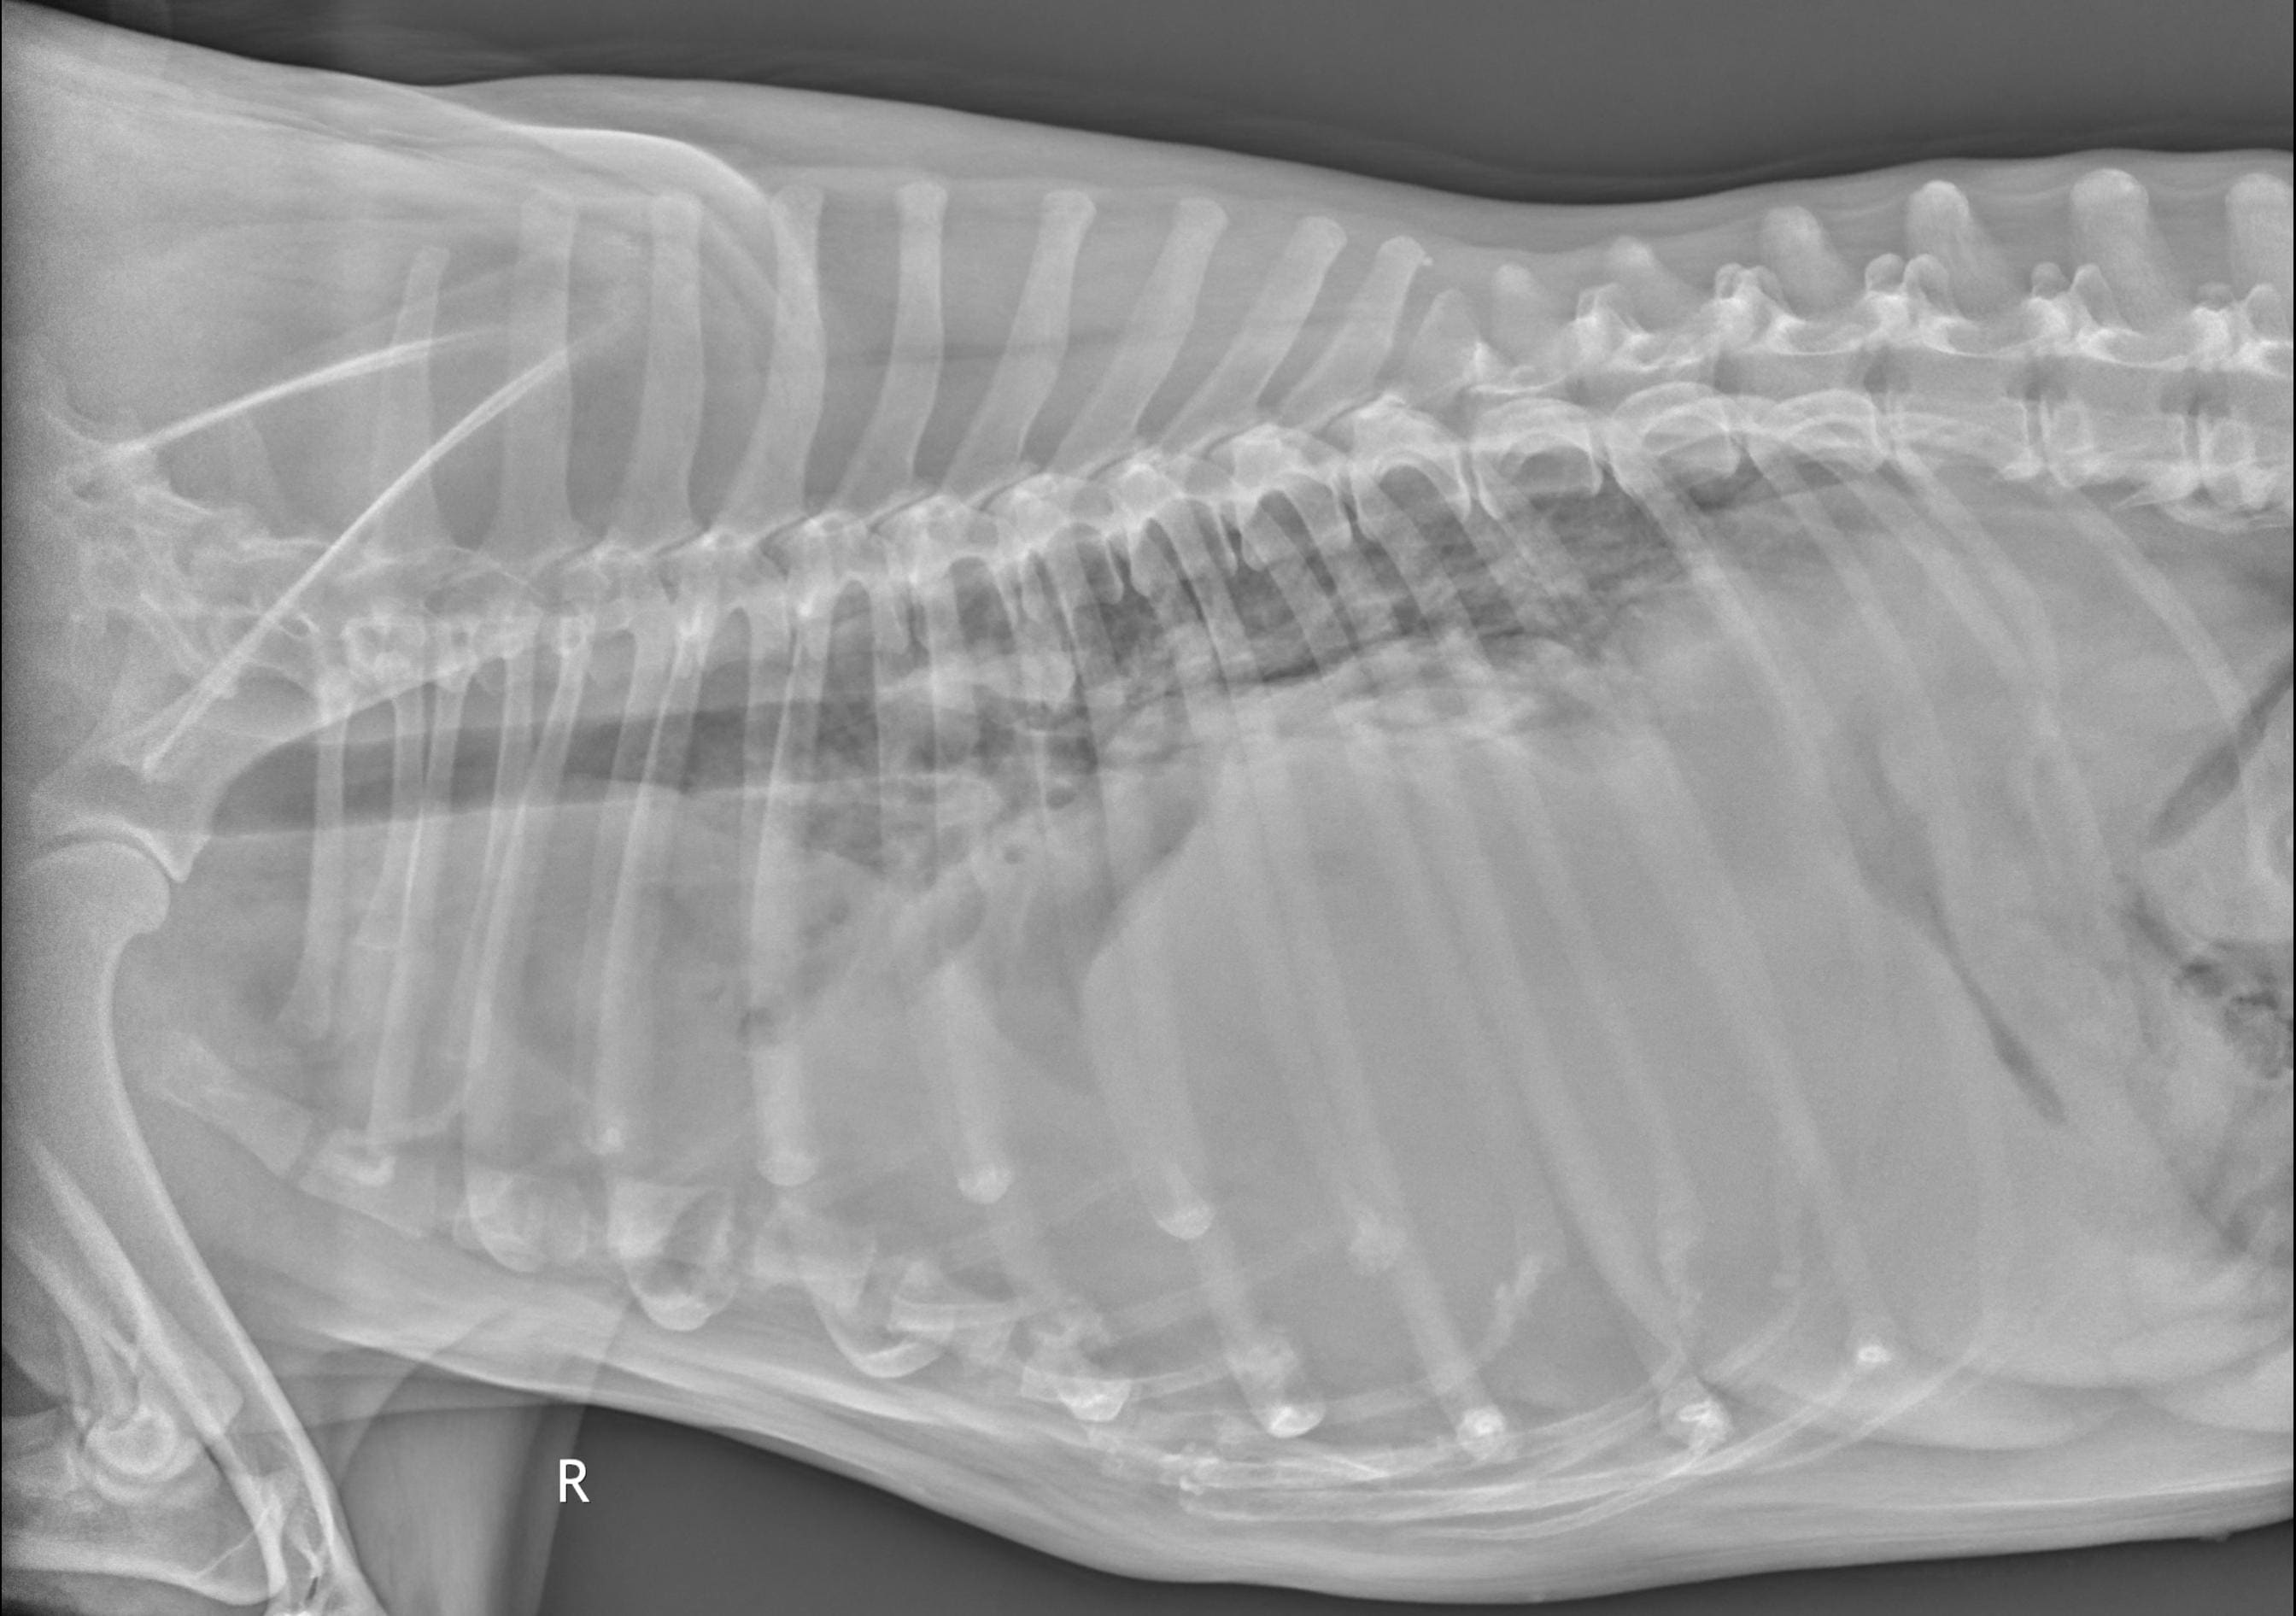

I am in a lot of pain today. My 10yo spayed female dog has had difficulty breathing for about a month or so (getting worse every day) and has lost a lot of weight, although she eats and drinks normally. Vet found severe pleural effusion and drained it (a large dog food bowl worth) and it was bloody, not a good sign. Attached are the x-rays taken today and I would like to know what your opinion is on prognosis and whether it would be wise and humane to pursue this or I should let her go.

Poor Xica! I'm so sorry that she's sick, and that you're in the position of having to consider what is best for her right now. This is always a difficult situation. Her x-rays do appear to show very severe pleural effusion. As I'm sure your veterinarian has probably discussed with you, pleural effusion of the type that you have described (bloody fluid) is almost always caused by one of two things: congestive heart failure, or cancer. The amount of fluid in her chest makes it hard to get a good look at the size and shape of her heart, or to determine if there are any obvious tumors in her chest, so it's hard to say which of these possibilities is more likely without additional testing. But unfortunately, even with aggressive treatment, neither of them have a good long-term prognosis. Knowing this, if I were in your position, I believe I would probably decide to let her go rather than pursuing hospitalization, chest tube placement, etc. - these are invasive, uncomfortable procedures that are unlikely to make a significant difference in the outcome for her, because of the severity of her underlying disease. That being said, the decision of when to consider euthanasia is a very personal choice, and one that is different for every pet owner. If you feel that you need to do everything possible, and want to pursue advanced diagnostics to try and get a more specific answer as to what's wrong, there is nothing wrong with this at all - but if you were my client, I would try to gently caution you that her underlying condition will almost certainly be fatal regardless of what you do. I hope you're able to find peace in your decision, whatever it might be.

These xrays show a number of very concerning findings and the weight loss is a confounding factor. Her prognosis is very poor and if draining the chest has not provided significant relief of her symptoms then yes, euthanasia may be the kind option for Xica. Curative treatment is extremely unlikely and if her respiratory symptoms were not completely resolved with draining then medical management is not expected to maintain adequate comfort either. Remember all the good times she has given you and take comfort in your ability to release her from pain and discomfort at the appropriate time